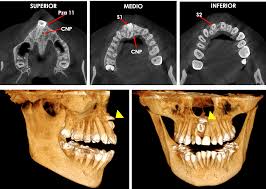

Planificación 3D y tomografía

Con tomografía computarizada 3D planificamos la posición exacta de cada implante. Visualizamos nervios, hueso y estructuras anatómicas para una cirugía segura y predecible.